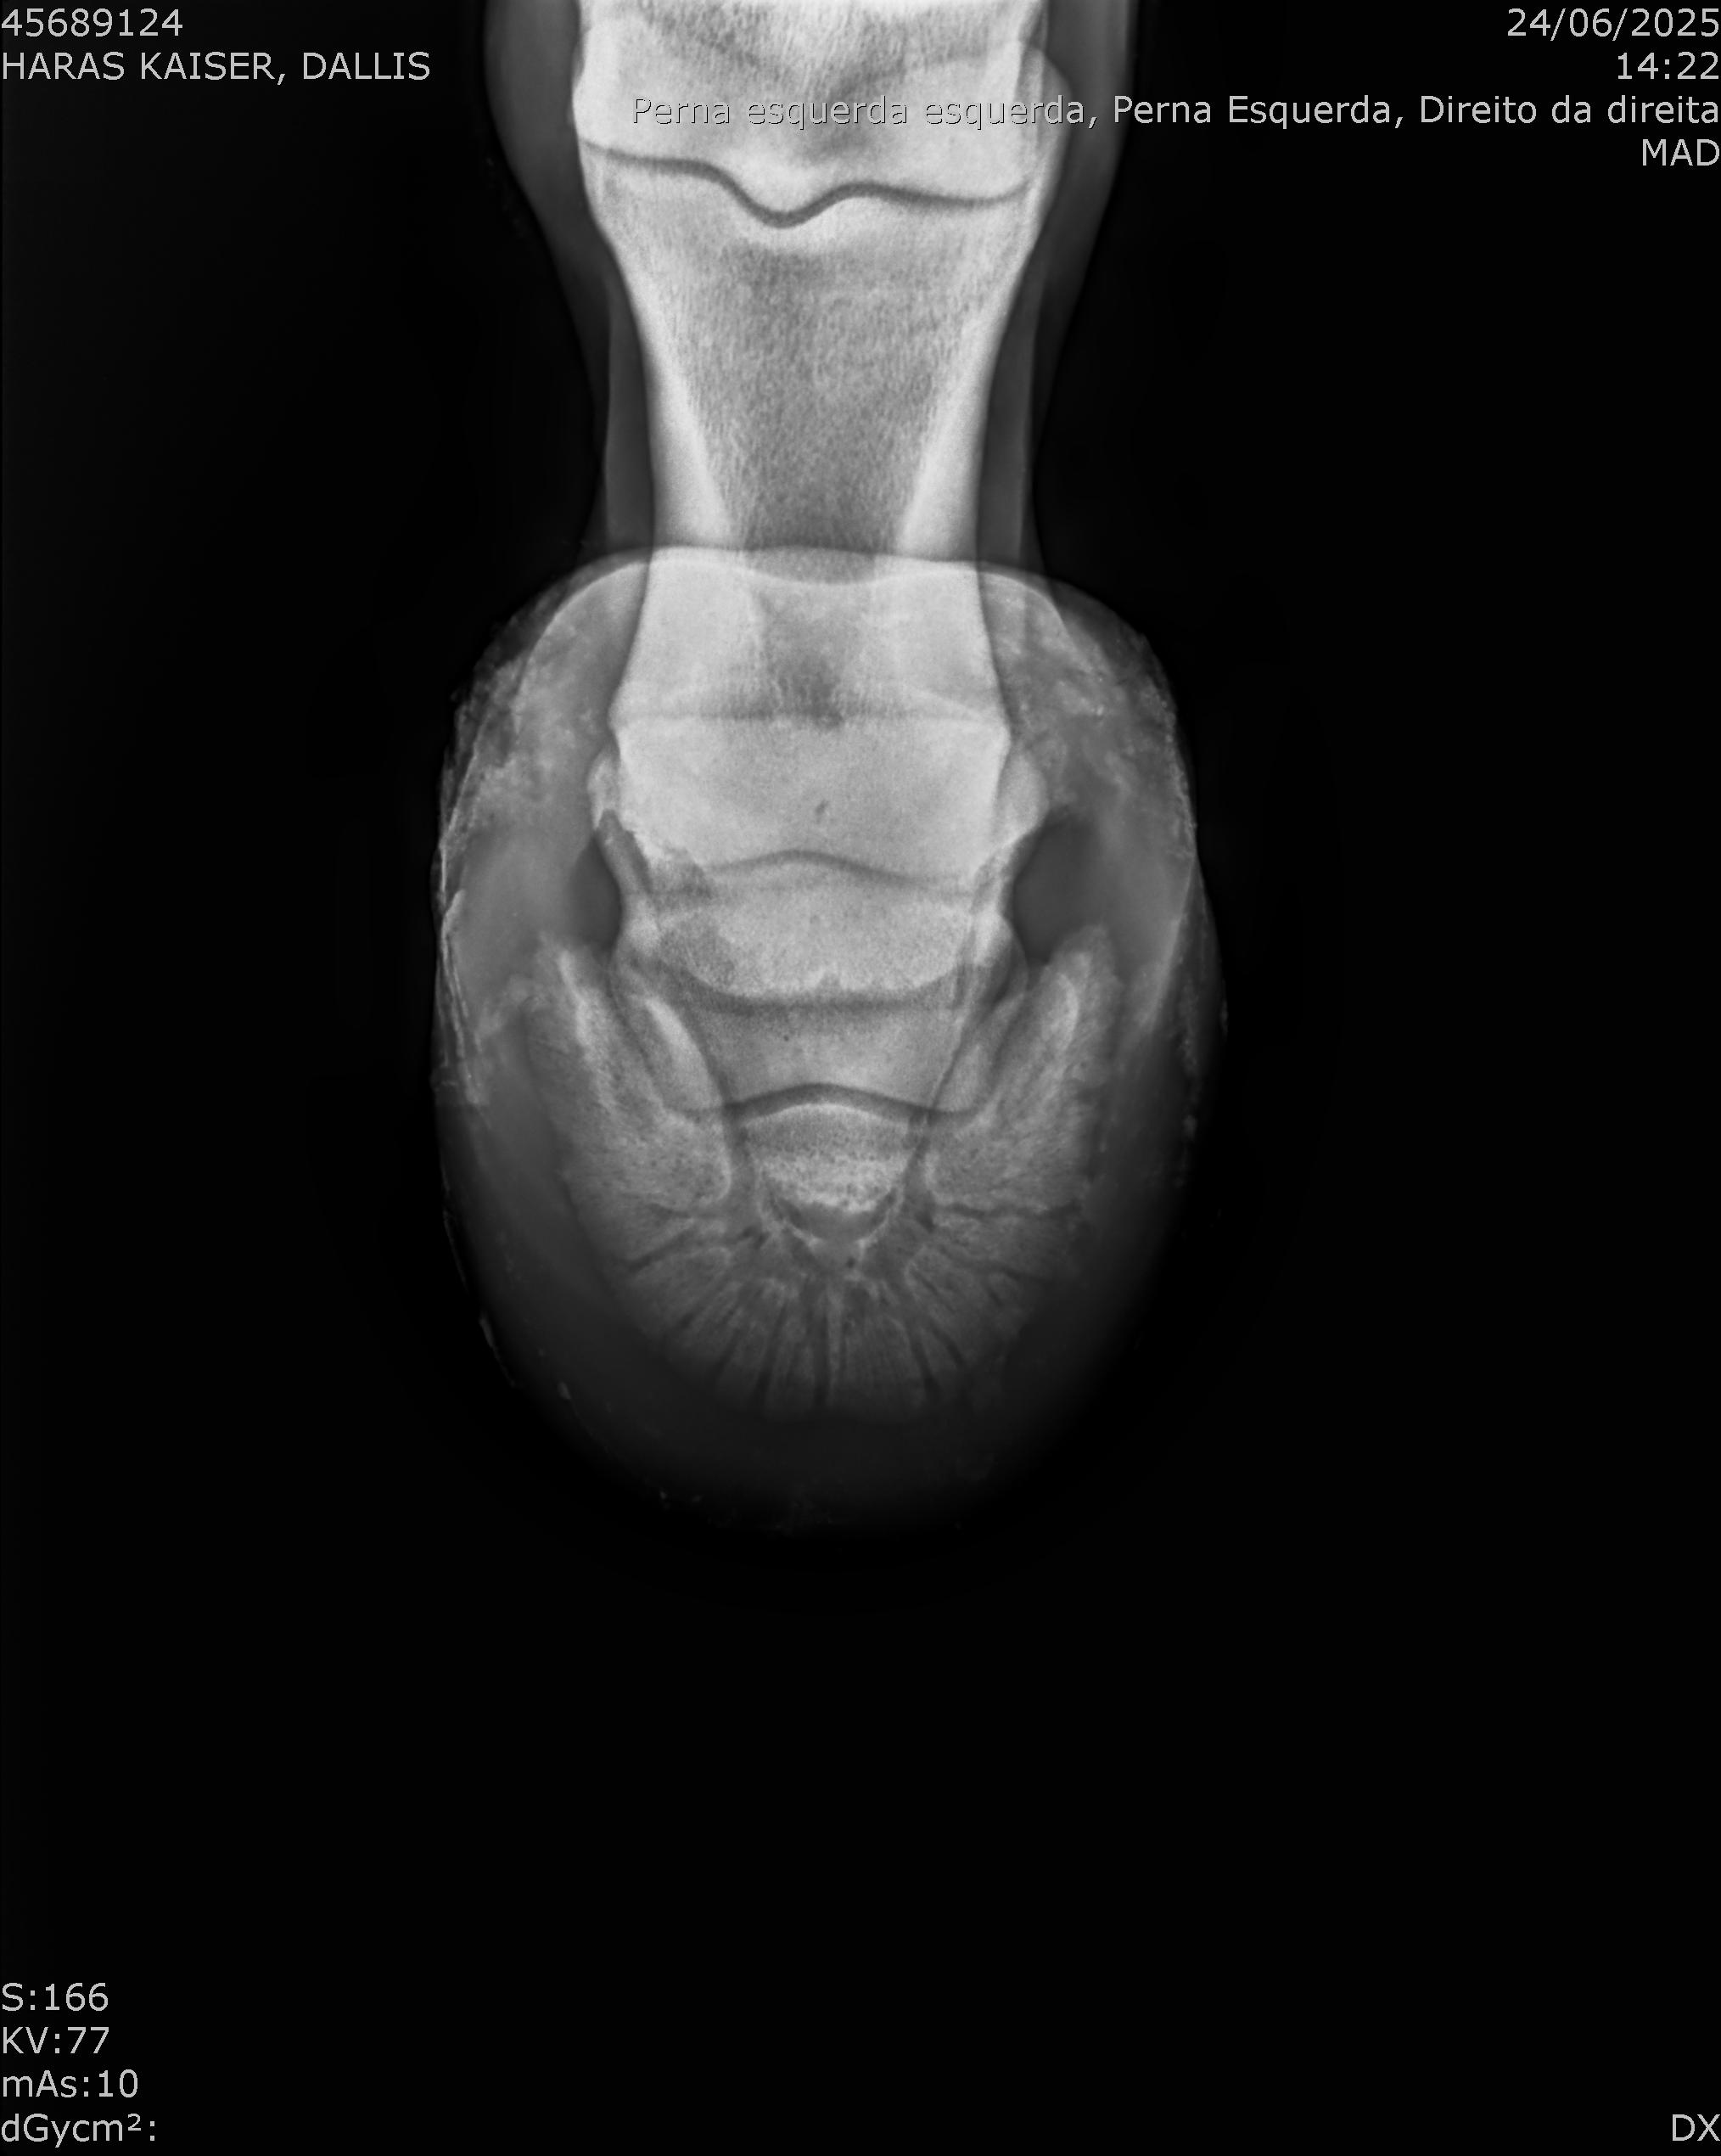

:: RAIOS-X DO LOTE